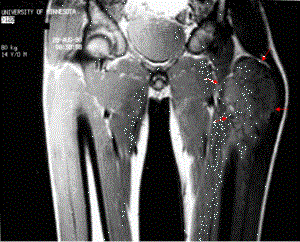

Sarcomul Ewing

Sarcomul Ewing este o tumor? malign? osoas?, sovaldi buy ce se poate întinde ?i la ?esuturile moi din jur.

A fost descrisă pentru prima dată de către James Ewing în 1921, fiind cunoscută şi sub denumirea de PNET (Peripheral primitive neuroectodermal tumors). Sarcomul Ewing poate afecta orice os din organism, dar se localizează mai frecvent la nivelul oaselor pelvisului, coapsei, extremităţii proximale a membrului superior, extremităţii distale a membrului inferior şi la nivelul coastelor.

Diagnosticul se pune în urma examenului clinic şi testelor paraclinice (în special radiografie osoasă). În afara radiografiei osoase se practică şi CT şi RMN, în scopul delimitării tumorii, dar şi evidenţierii metastazelor. Pentru diagnosticul precis se va face biopsie osoasă şi examen anatomopatologic. Pentru descoperirea metastazelor medulare se va practica biopsia medulară. Deoarece sarcomul Ewing este asociat cu metastazele pulmonare se va efectua şi o radiografie pulmonară.